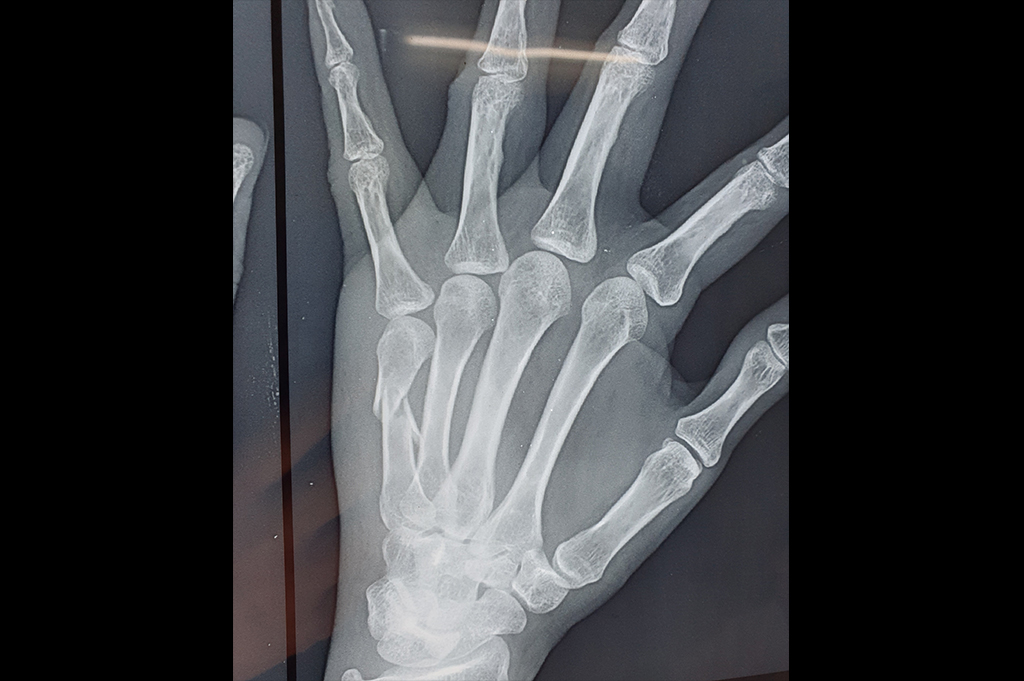

Metacarpal Fracture – External Fixator JESS